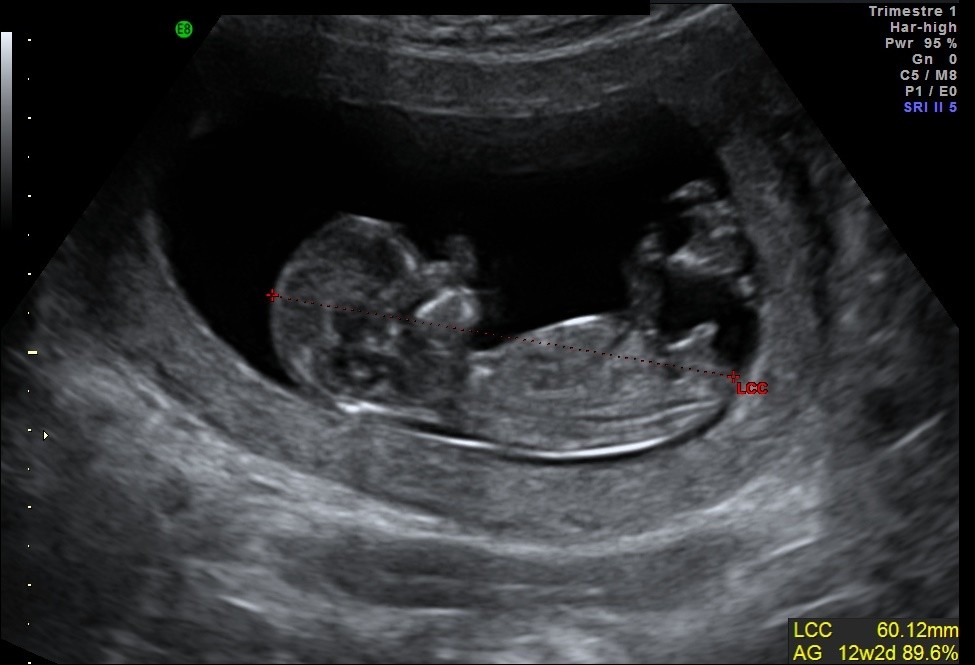

Longueur Cranio Caudale